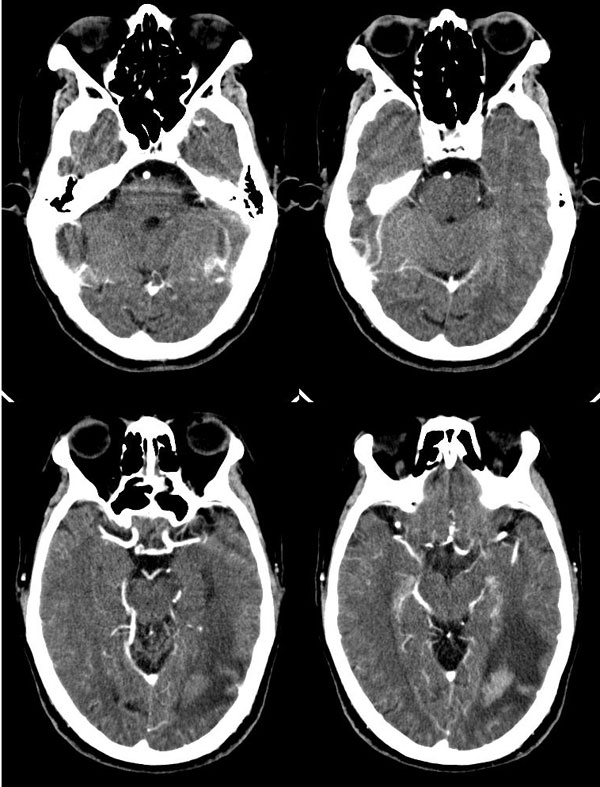

胼胝体见多个明显强化结节影,周围水肿轻,左颞枕交界区见呈腊肠状强化灶,周围水肿明显,多发病灶均有占位效应,首先考虑淋巴瘤,水肿轻,位置深,强化明显,其次转移瘤?

此病人应该是老年人:脑沟脑回加深增宽,尤其是双侧外侧裂池增宽明显.

胼胝体见多个明显强化结节影,周围见低密度水肿灶;左颞枕交界区见呈腊肠状强化灶,增强后强化明显,周围指状水肿。多发病灶均有占位效应,水肿轻,位置深,强化明显。

胼胝体膝部及压部各见一明显强化结节影,周围水肿轻,左颞枕交界区见呈腊肠状强化灶,周围水肿明显,多发病灶均有占位效应。

左颞枕交界区及胼胝体多发明显而均匀强化的实性肿块。

沟脑回加深增宽证像,特别是双侧外侧裂池增宽明显,因是老年患者,病灶位置深且都在侧脑室旁,呈腊肠状,边界清,有轻占位和水肿。

首先考虑淋巴瘤;转移瘤也可考虑,但病灶虽为多发,但位置深在,与其好发于大脑皮质及皮质下区的特点不符。